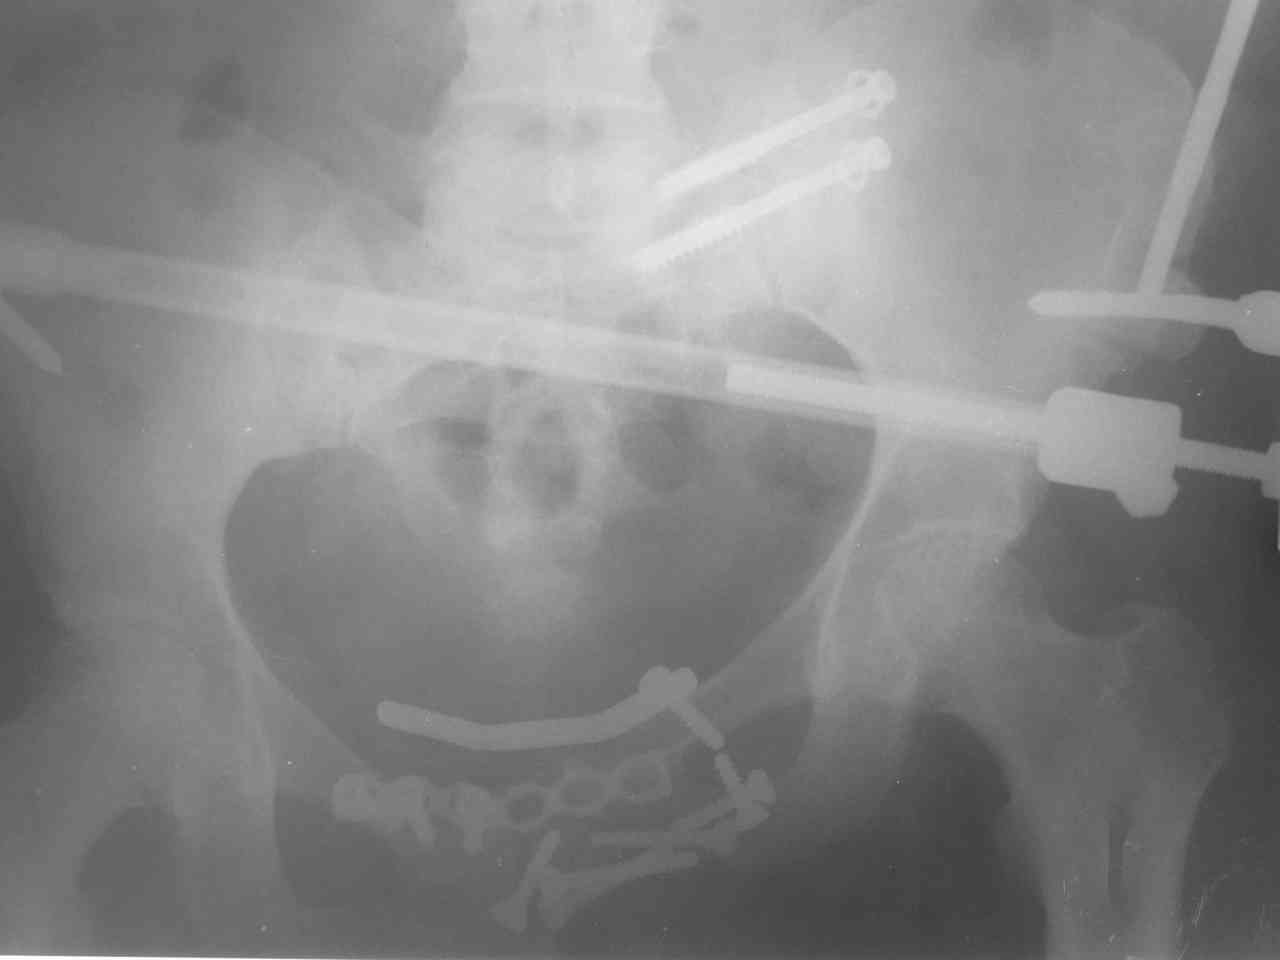

Пациентка получила травму таза 9 месяцев назад (перелом латеральной

массы крестца слева, разрыв лонного сочленения). Лечилась в стационаре

другого города, без успеха. В мае 2007 прооперирована в нашем

отделении, выполнена открытая репозиция повреждений, остеосинтез

винтами латеральной массы крестца и пластинами лонного сочленения.

Дополнительная  фиксация аппаратом внешней фиксации. 3 недели спустя

упала в палате на ягодицы, при этом получила повторную травму таза,

смещение отломков. Уважаемые коллеги каково ваше мнение о способе

фиксации полученных повреждений. С уважением Алексей.